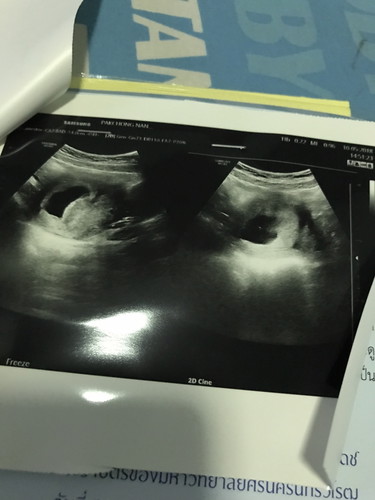

มาแชร์ประสบการณ์ การเป็นท้องลมค่ะ ท้องแรก เมื่อปีที่แล้ว. ประจำเดือนไม่มา เราก็ตรวจปรากฎว่า ขึ้น 2ขีด. และมีอาการแพ้เหมือนคนตั้งครรภ์. ต่อมาคุณหมอก็นัดซาวด์. แต่พอซาวด์ เจอถุงตั้งครรภ์ค่ะ แต่ไม่เจอตัวน้อง. ตอนนั้น 13 สัปดาห์แล้ว. คุณหมอให้แอดมิดและเหน็บยา ขูดมดลูก. ตอนนั้นเสียใจมากค่ะ. แต่ผ่านมา1ปี. ตอนนี้ ท้อง2ค่ะ รอบนี้ เห็นตัวน้อง และน้องก็เจริญเติบโต ปกติดีค่ะ. ฝากถึงแม่ๆที่เจอสภาวะเดียวกัน ไม่ต้องกังวลน่ะค่ะ. หลังจากที่เป็นท้องลม เราก็ดูแลตัวเอง ทานอาหารให้เป็นประโยชน์ พักผ่อนให้เพียงพอ เพียงเท่านี้ สภาวะที่จะเกิด ก็อาจจะน้อยลงค่ะ. และน้องก็จะมาเองค่ะ ✌?❤️

1 baby